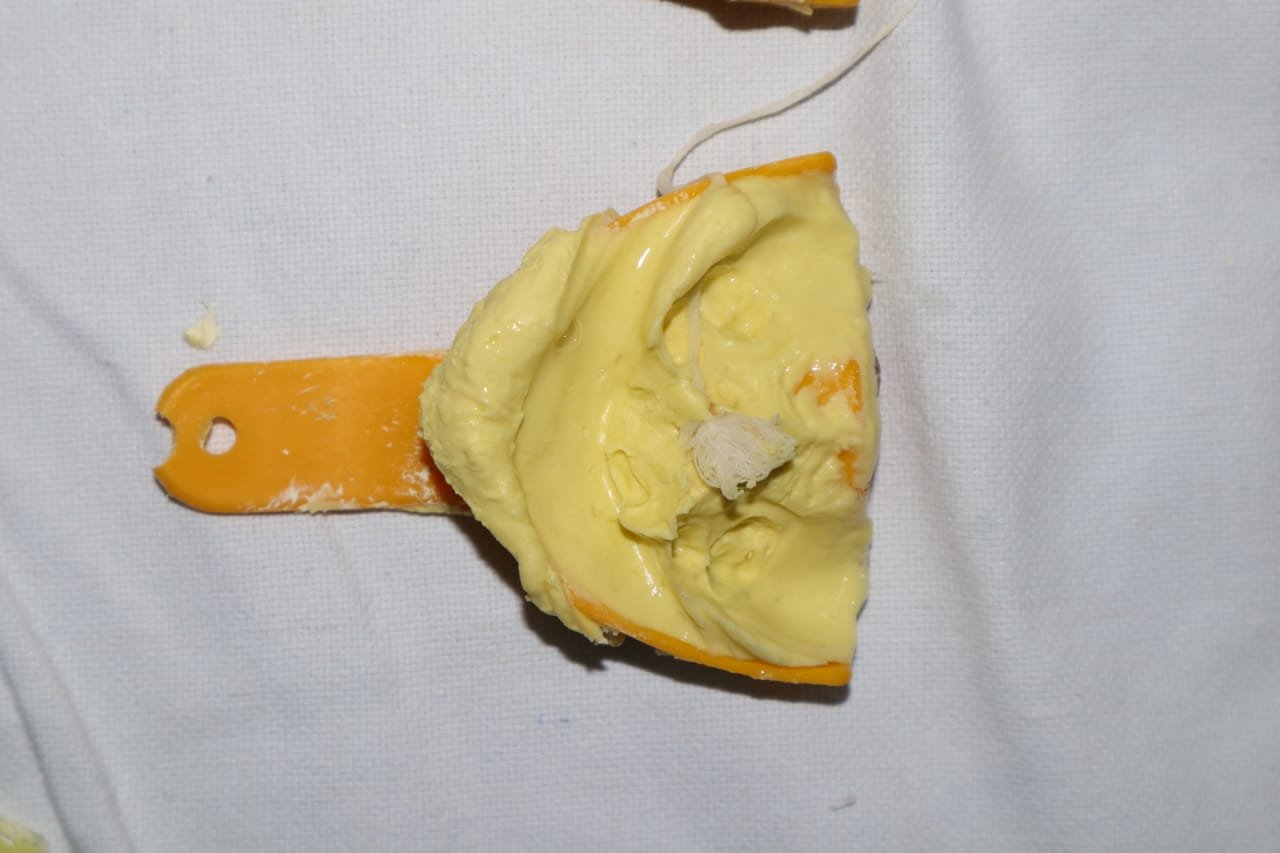

"Step into our world of healthy smiles! At Kreative Dental Care, we believe every smile tells a story. Explore our gallery to see glimpses of our clinic, advanced facilities, happy patients, and memorable moments from events, recognitions, and community initiatives."